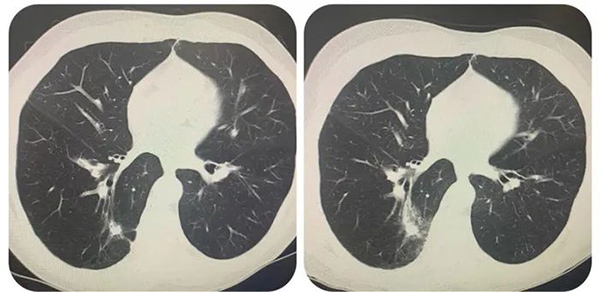

一位70岁老年男性,因发现右下肺占位,大小1.5×0.9cm。在应急总医院实施支气管镜下冷冻肺活检(transbronchial cryobiopsy,TBCB),活检病理:腺癌。既往慢性阻塞性肺病史,肺功能重度减低。患者及家属考虑患者基础肺功能差,如手术治疗会影响生活质量,故拒绝行手术切除,故给予行支气管镜下射频消融术。术后复查胸部CT提示靶区覆盖面积100%。